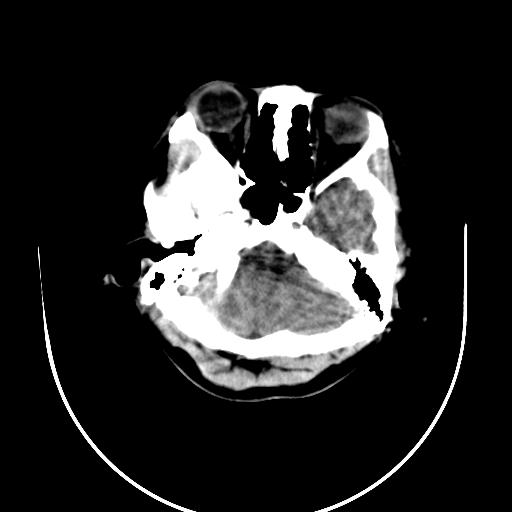

标题: CT10010:女/24岁,癫痫一周,发作时间不固定. [打印本页]

标题: CT10010:女/24岁,癫痫一周,发作时间不固定.

右侧额叶正常吗?

右额叶镰旁饱满.

右侧外侧沟?中央沟?可能有问题,不知以前有没有癫痫过,最好是增强下,排除局部血管畸形等病变

倒数第6幅图中线结构有点偏,而侧脑室额角未见异常,可结合增强扫描。